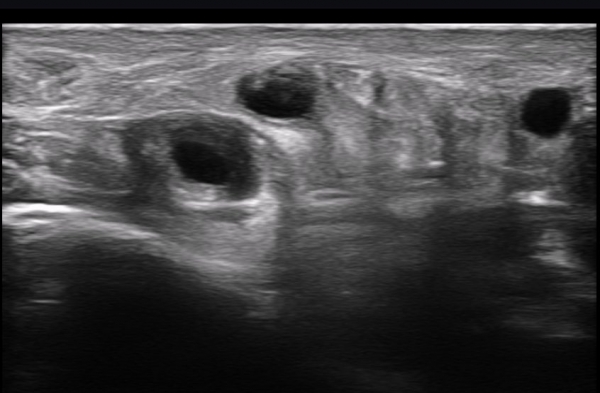

ÃÊÀ½ÆÄ ¼Ò°ß : ºñº¹½Å°æ Ⱦ´Ü¸é°Ë»ç¿¡¼­(»çÁø 1~13) ºñº¹½Å°æÀÇ Àú¿¡ÄÚ ºÎÁ¾°ú ´Üºñ°ñ°Ç³» ³¶Á¾¼º º´º¯ÀÌ °üÂûµÈ´Ù.